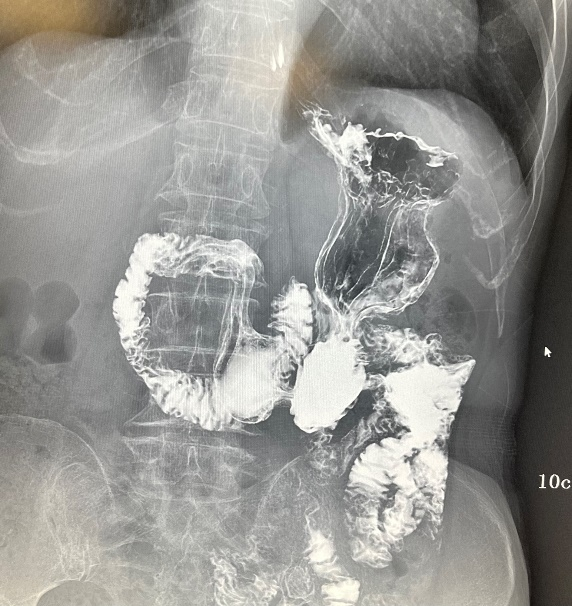

(三)下消化道造影

用于直肠、结肠及回盲部病变的造影诊断(气钡剂双重造影)。